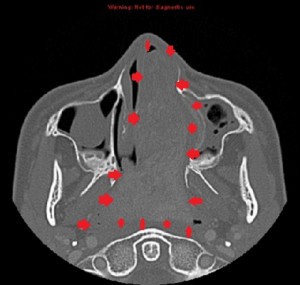

Radiologic findings

First panel, left to right: Axial contrast-enhanced maxillofacial CT scan in soft-tissue window from superior to inferior, showing a large, avidly enhancing mass in the left nasal fossa, extending posteriorly into the left nasopharnx and crossing into the right nasopharynx behind the nasal septum. Note opacification of the right and left maxillary sinuses, possibly from disturbed drainage.

Second panel, left to right: The same set of images as in the first panel, but in bone window, showing bowing of the medial wall of the left maxillary sinus and opacified maxillary sinuses. There is no bone destruction or invasion.